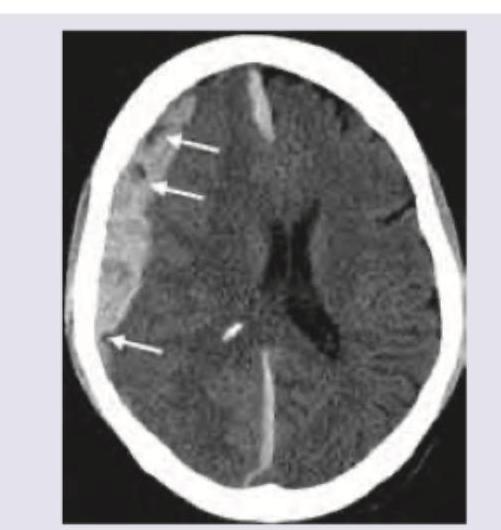

A mixed martial arts boxer lost his match by knockout. One week later, he is having daily headaches, vomiting and disorientation. On arrival in casualty $\mathrm{GCS}=7$ and fundus shows presence of papilledema. Urgent CT scan head shows?

Explanation: ***Subdural bleed*** - The CT scan image shows a **crescent-shaped collection** of blood over the surface of the brain, which is characteristic of a **subdural hematoma**. The symptoms developing a week after impact ("knockout") are consistent with a subacute presentation of a subdural hematoma, which can gradually expand and cause increased intracranial pressure (manifesting as headaches, vomiting, disorientation, papilledema, and decreased GCS). - Subdural bleeds typically result from the tearing of **bridging veins** traversing the subdural space, often seen in trauma, particularly in patients with brain atrophy (such as elderly or chronic alcoholics). *Lobar bleeding* - **Lobar bleeding** refers to intraparenchymal hemorrhages within a specific lobe of the brain. On CT, this would appear as a focal, high-density collection *within* the brain parenchyma, not along its surface in a crescent shape. - The clinical picture of gradual neurological decline and signs of increased intracranial pressure are more consistent with an expanding subdural hematoma than an isolated lobar bleed, which typically presents more acutely with focal neurological deficits. *Intraparenchymal bleeding* - **Intraparenchymal bleeding** is hemorrhage directly within the brain tissue. On CT, it presents as a high-density area *within* the brain substance itself, often irregular in shape. - While trauma can cause intraparenchymal bleeds, the image clearly shows an extravascular collection *outside* the brain parenchyma, between the dura mater and arachnoid mater. *Subarachnoid bleed* - A **subarachnoid hemorrhage (SAH)** would appear on CT as high attenuation (blood) within the **sulci and basal cisterns** of the brain, following the contours of the subarachnoid space. This is not seen in the provided image. - SAH typically presents with a sudden, severe "thunderclap headache" and meningism, which differs from the more gradual onset of symptoms described with associated disorientation and papilledema (suggesting a lesion causing mass effect).